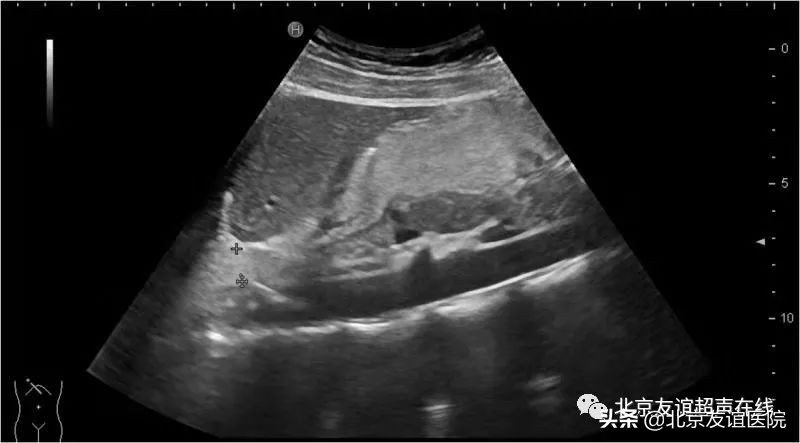

超声科作为协作组的一员,充当了对胃食管反流病初步筛查的角色。在实时超声监测下,可以发现超声造影剂由胃腔反流入食管下段,从而初步的诊断胃食管反流。

超声还可以筛查造成胃食管反流的风险因素:食管裂孔疝,贲门失弛缓,胃潴留,十二指肠胃胆汁反流,十二指肠淤滞,食管胃底静脉曲张等。